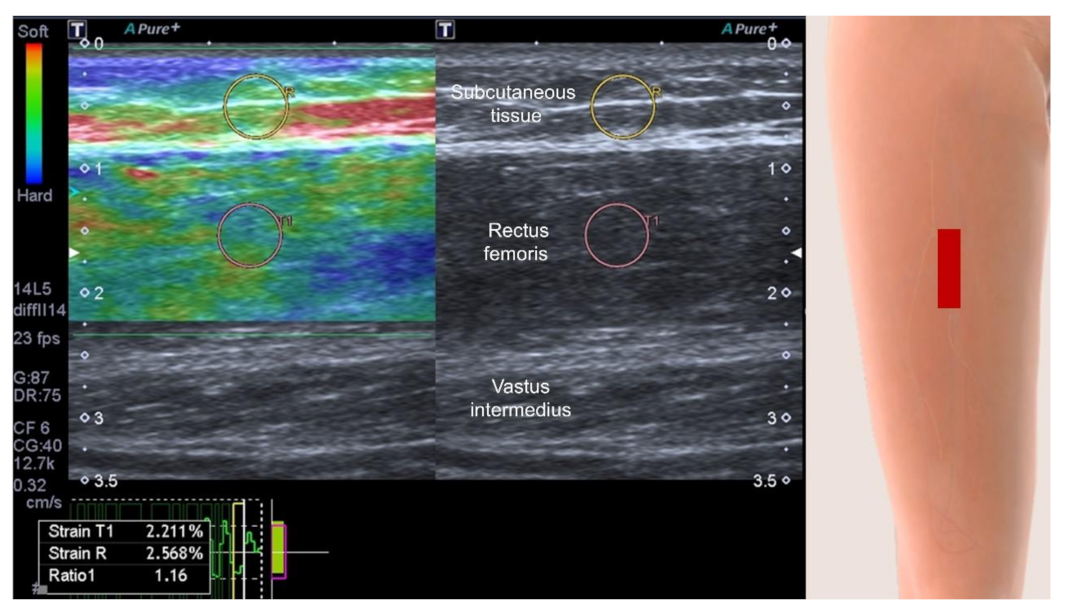

3.4.4. Muscle Stiffness Measurement by Sonoelastography

- Janczyk, E.M.; Champigny, N.; Michel, E.; Raffaelli, C.; Annweiler, C.; Zory, R.; Guérin, O.; Sacco, G. Sonoelastography to Assess Muscular Stiffness Among Older Adults and its Use for the Diagnosis of Sarcopenia: A Systematic Review. Ultraschall Med. 2021, 42, 634–642. [Google Scholar] [CrossRef]

- Bastijns, S.; De Cock, A.M.; Vandewoude, M.; Perkisas, S. Usability and Pitfalls of Shear-Wave Elastography for Evaluation of Muscle Quality and Its Potential in Assessing Sarcopenia: A Review. Ultrasound Med. Biol. 2020, 46, 2891–2907. [Google Scholar] [CrossRef] [PubMed]